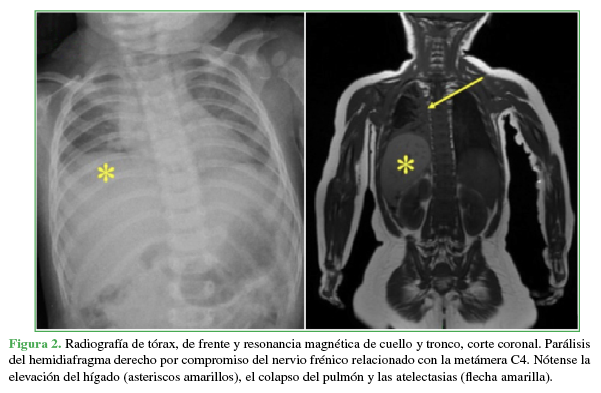

Niña de 9 meses, víctima de un accidente automovilístico. Su madre, sentada en la butaca del acompañante y con el cinturón de seguridad colocado, llevaba a la niña en brazos sobre su falda. Llegó derivada desde otro centro asistencial, con 48 h de evolución. El examen al ingresar reveló un puntaje 13 en la escala de Glasgow, parálisis de ambos miembros superiores con nivel metamérico C5, pero con respuesta a estímulos nociceptivos, indemnidad neurológica de tronco y de miembros inferiores, dificultad respiratoria con neta disminución de la entrada de aire en el hemitórax derecho. Los estudios iniciales incluyeron radiografías de columna cervical y tórax, y resonancia magnética (RM) de ambas regiones.

HALLAZGOS E INTERPRETACIÓN DE LOS ESTUDIOS POR IMÁGENES

En las radiografías anteroposterior y de perfil, de columna cervical, no se observaron anomalías. El trazado de las cuatro líneas sagitales recomendadas en el trauma era normal. Sin embargo, la relación facetaria C2-C3 era dudosa (Figura 1). La disminución de la entrada de aire en el hemitórax derecho se relacionó con una parálisis diafragmática y atelectasia pulmonar masiva (Figura 2). La RM de columna cervical y base del cráneo reveló una epifisiólisis del axis, una lesión ligamentaria posterior y un importante edema perivertebral (Figura 3).